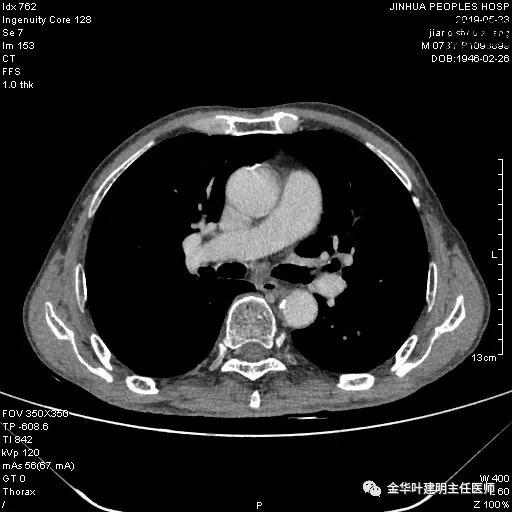

考虑左侧大量胸腔积液,遂进一步胸部CT检查:

以上是肺窗表现,下面为纵隔窗影像: